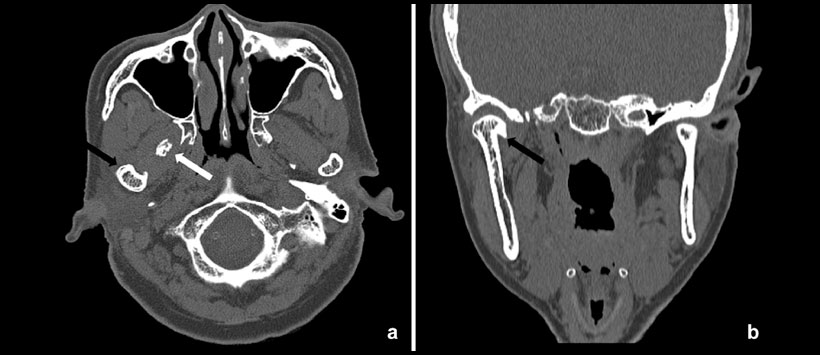

Figura 2: Tomografía Computarizada (TC) revelaron hiperplasia y esclerosis de la región anterior del cóndilo (flechas negras) y un cuerpo calcificado (flecha blanca) en los cortes axiales (a) y coronales (b)

Figura 3: Tomografía Computarizada (TC) en el que se observa ensanchamiento del espacio articular (flecha negra) en la ATM derecha (a) en comparación con la ATM izquierda (b)